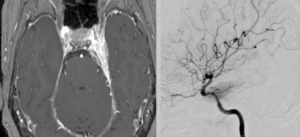

2026年1月 71歳女性の頭蓋咽頭種を内視鏡で摘出しました。 2026 3/01 聴神経・腫瘍 2026年3月1日川尻先生の執刀で嚢胞性かつ小型の頭蓋咽頭腫を内視鏡で摘出しました。新しく入局する高嶋浩央先生も手術に参加しました。術後髄液漏が生じ修復術が必要となりましたが、後遺症なく退院しました。学生らも熱心に見学していました。 聴神経・腫瘍 よかったらシェアしてね! URLをコピーしました! URLをコピーしました! 56歳女性 内頸動脈眼動脈分岐部動脈瘤クリッピング術をしました。軽度視野欠損が出ましたが無事退院されました。 260125日 大雪となりました。 この記事を書いた人 kikuta 関連記事 2604月、59歳女性の左海綿静脈洞内髄膜腫(複視)に対して左内頸動脈のための左STA-MCAバイパスを行いました。 2026年4月11日 260331 60歳男性 頭蓋咽頭腫を開頭で摘出しました。 2026年4月3日 260324 78歳男性 大型下垂体腺腫を外視鏡+内視鏡の複合手術を行いました。 2026年3月26日 2026年2月 74歳女性右聴神経腫瘍の手術を行いました。 2026年3月21日 37歳女性 下垂体線腫を内視鏡手術しました。両耳側の視野欠損が回復しました。 2025年12月27日 66歳大型の聴神経腫瘍、術中出血のため手術が難渋し時間がかかりました。過去最大級の難敵でした。 MRIだけでは分からないものです。 2025年12月16日 13歳小児の小脳腫瘍の摘出を行いました。術後失調や眼振が出ていましたが徐々に回復され大きな後遺症なく回復されました。よかったです。 2025年12月16日 27歳女性 第四脳室髄膜腫を手術しました。術後左顔面まひ、外転神経麻痺が出現しましたが、顔面は数日で治癒しました。 2025年12月6日